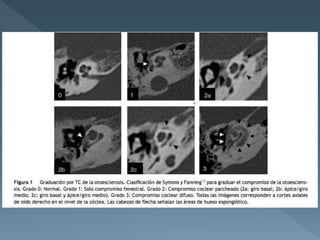

 TC simple de hueso temporal

 RM (realce cercano a ventanas oval y

redonda-fenestral.

 Demuestran de manera objetiva los focos de

otosclerosis.

 TC simplede hueso temporal  RM (realce cercano a ventanas oval y redonda-fenestral.  Demuestran de manera objetiva los focos de otosclerosis.